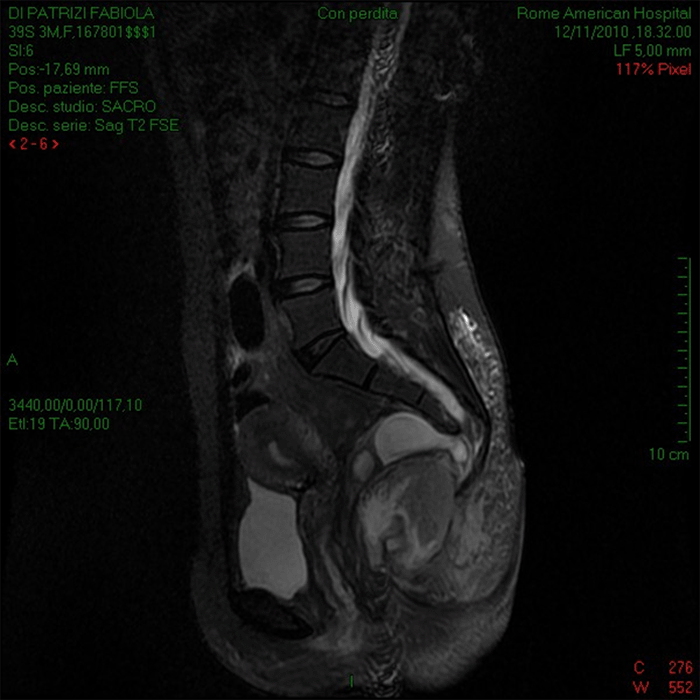

The retrorectal cavity was bluntly entered. There was no presence of methylene blue in the abscess cavity. The draining purulent material was sent for culture and cytology. The pus was totally evacuated, and the cavity was washed with saline solution—attention was paid to not touch the meningocele. Histology of the abscess wall revealed a diffuse inflamed necrotic wall. Antibiotic therapy was continued with ceftriaxone 2 g/day, metronidazole 1.5 g/day, and amikacin 1 g/day. Escherichia coli was cultured from the abscess cavity. The patient was discharged after ten days without pain, fever, or headache. Follow up at 3, 6, 12, 24, and 36 months revealed an asymptomatic patient (Figure 4).

Figure 4. Follow-up MRI Showing Resolution of Retrorectal Abscess and Expansion of Meningocele. Published with Permission